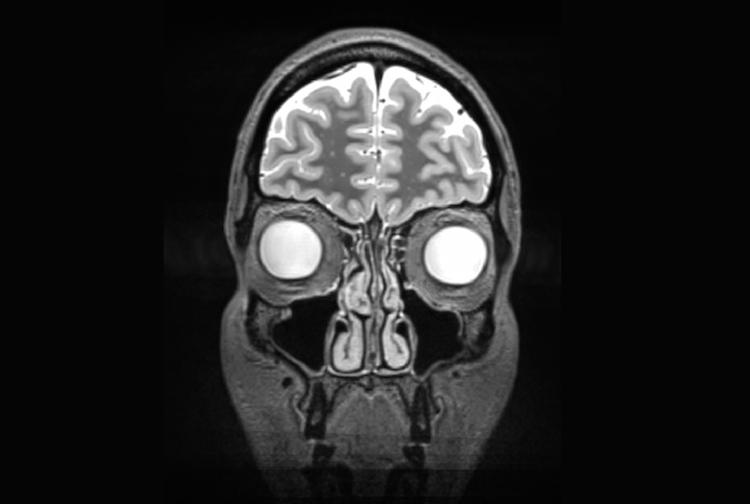

Poldrack’s brain on caffeine and no food. Poldrack’s brain on caffeine and food. (Poldrack et. al.)

Poldrack’s team found more connectivity in certain networks of the brain -- particularly between systems associated with movement and vision -- if he didn’t have breakfast and coffee. Poldrack says that’s surprising: “If anything we would have predicted that if you’re tired and caffeinated, connectivity would have gone down.” Figuring out why this effect occurred might be a fruitful avenue for research.